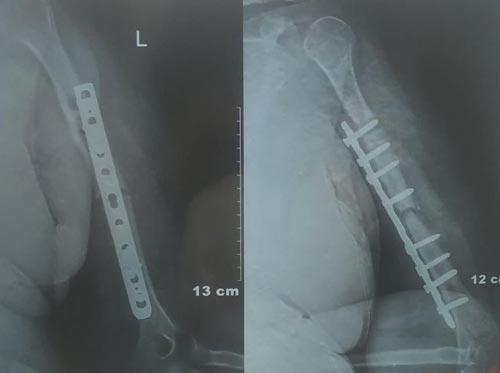

A bone fracture that is not currently healed and which will not even heal in the future is known as non-union. The non-union fractures are defined when there is no 9-month post occurrence or healing and has not shown any progress for three months.

Recovery and hospital stay at orthopedic hospital of a patient depends on the healing progress after orthopedic surgery which is determined by doctors by taking X-rays.

The treatment of non-union depends on the types of fracture and reasons for non-healing in the patient. In some cases, surgery is not required for the healing as they are treated with braces and various non-invasion methods.